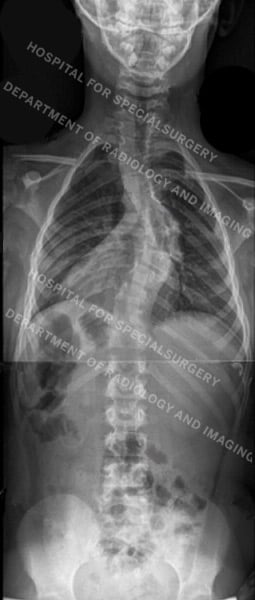

Posteroanterior (back-to-front) X-rays of dystrophic (first image) and nondystrophic scoliosis (second image)

In cases of dystrophic scoliosis, we typically see shorter, more sharply angulated curves. Characteristics of dystrophic scoliosis also include several bone abnormalities, including thinning of the ribs, significant rotation of the vertebrae, vertebral wedging, and erosion of the vertebrae by the spinal fluid, owing to the poor quality of the bone. Dystrophic scoliosis is also associated with kyphosis or a forward tilt of the spine, which can progress rapidly and may result in impingement of the spinal cord.